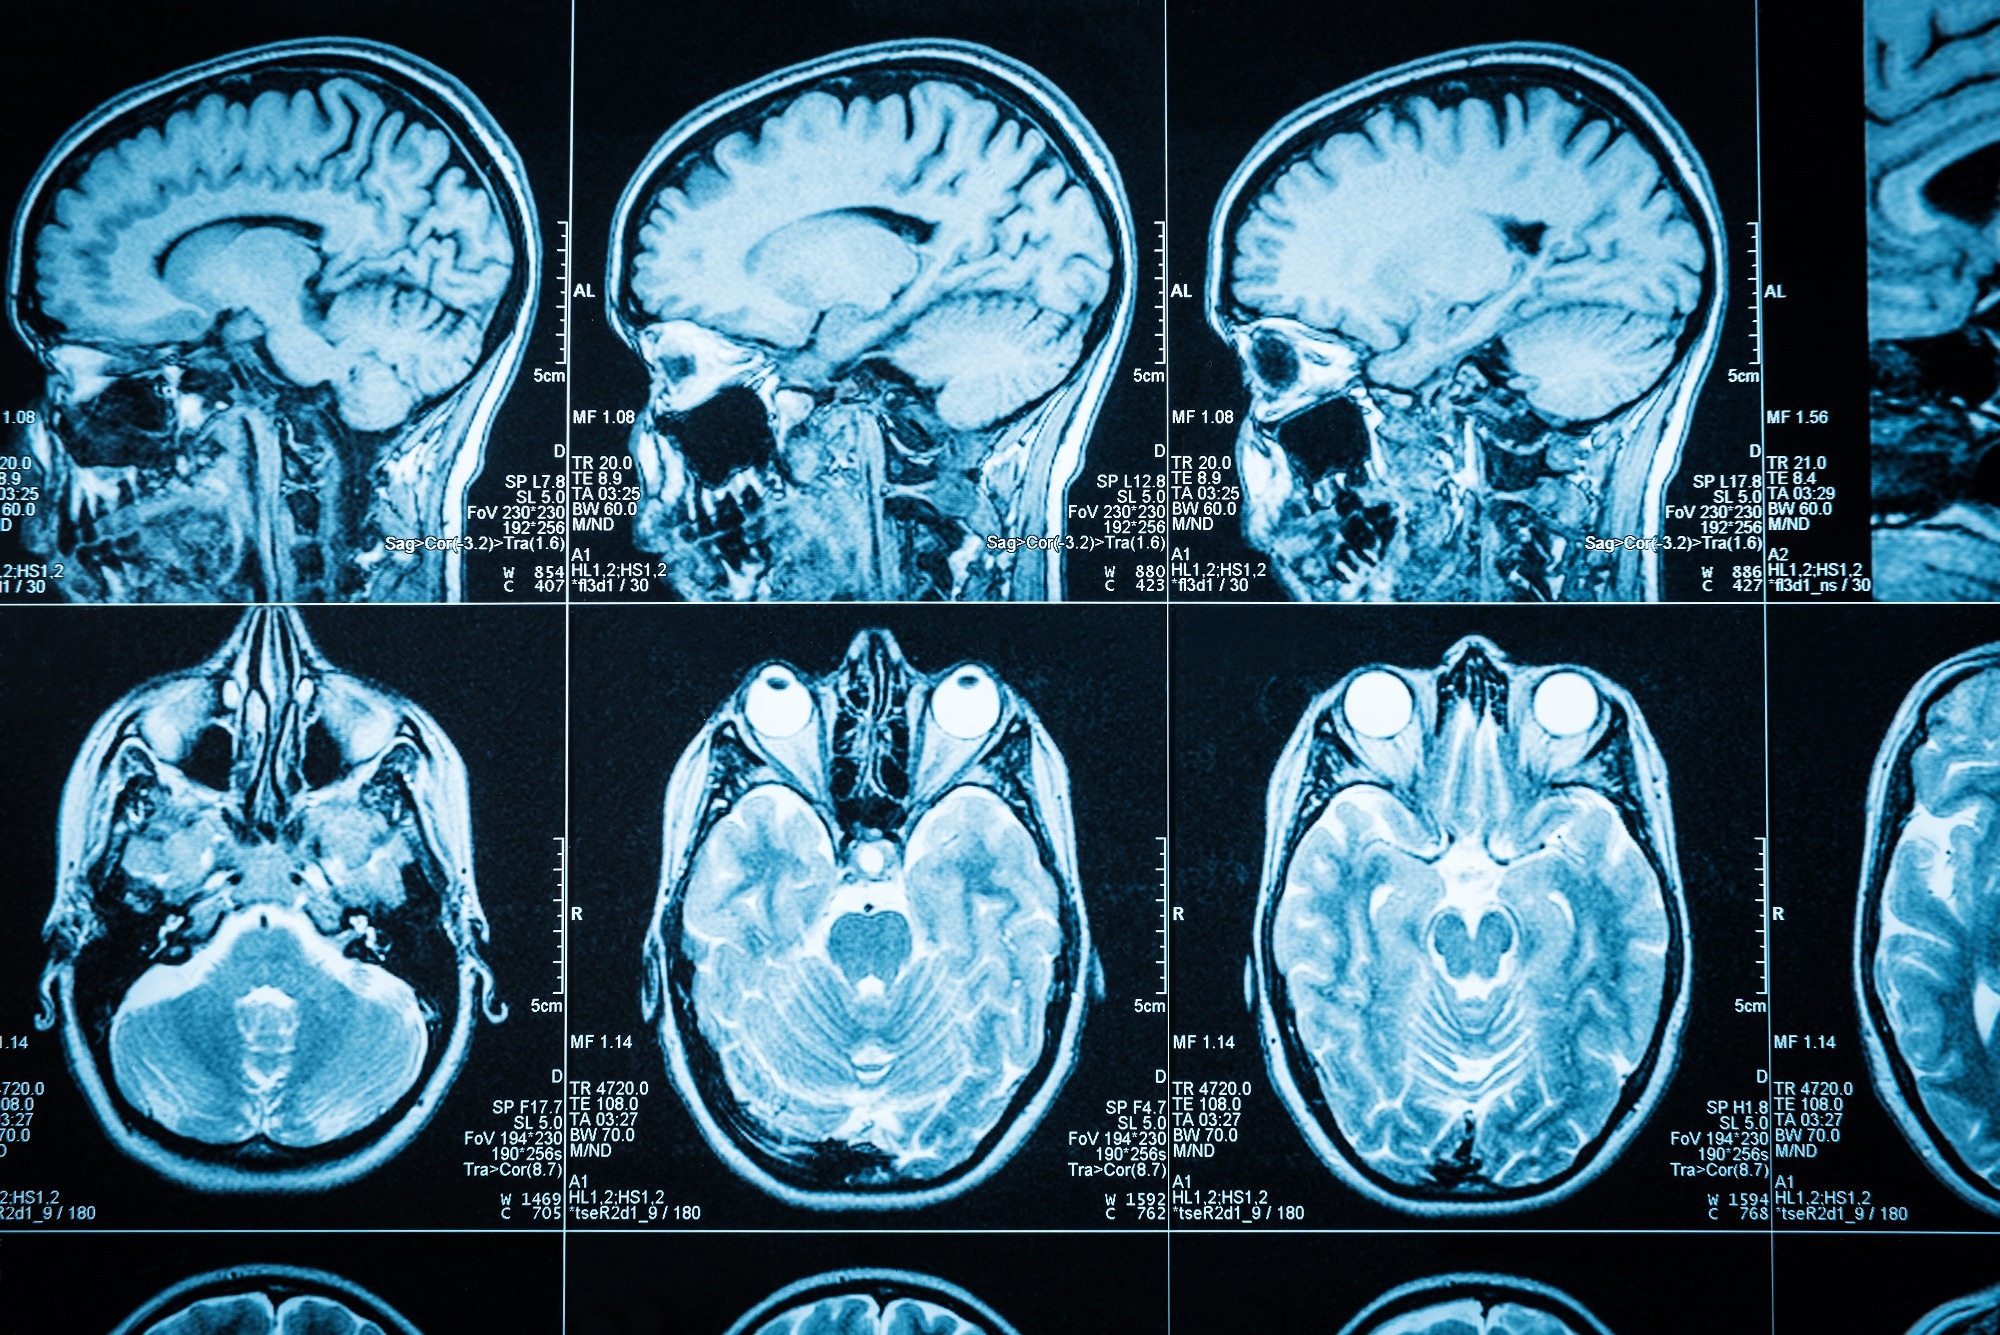

The diagnosis is commonly suspected on MRI with focal spinal cord displacement/buckling and, less frequently, on the direct sight of a cystic formation inside the spinal canal with signal patterns comparable to those of CSF.

With the widespread use of MRI, many lesions are now discovered by chance. MRI pinpoints the position and extent of spinal cord compression, but CT myelography (CTM) pinpoints the dural defect through which an extradural cyst communicates with the subarachnoid area.